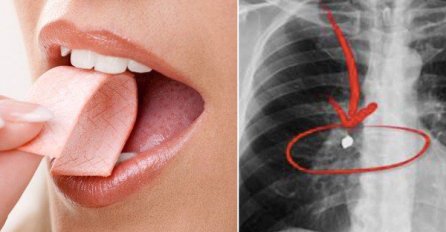

Kiosk 09.08.22. 13:08 Mislili ste da će vam se zalijepiti za crijeva, ali istina je drugačija: Evo šta se desi u stomaku kada progutate ŽVAKU Saznaj više